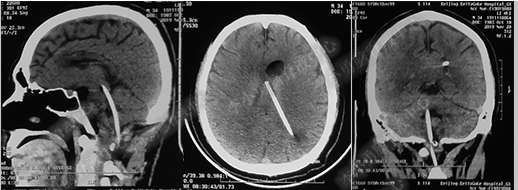

第4次出院后11天即2018年4月15日(分流术后284天,第2次的软性内镜术后179天),因引流管堵塞第5次住入该院,引流管内白色絮状物增多,引流管被堵塞。入院当天复查头部CT(图-10)显示脑室系统仍扩张。

图-10:2018年4月15日头部CT

第5次入院第2天即2018年4月17日,脑室腹壁外引流管堵塞,意识恶化,复查头部CT(图-11)示全脑室系统又较前扩大。当天急诊行左侧脑室穿刺外引流术。脑脊液化验外观黄色浑浊,并且送培养,结果是无菌生长。

图-11:2018年4月17日头部CT脑室扩张又加重

第5次入院第3天即2018年4月18日术后复查头部CT(图-12)显示脑室系统扩张较前好转。

图-12:2018年4月18日头部CT